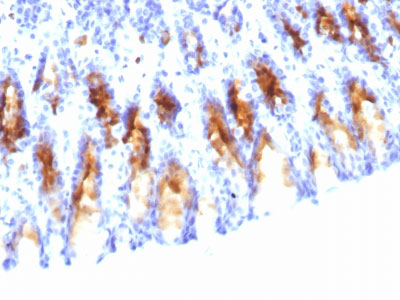

Formalin-fixed, paraffin-embedded human Stomach stained with MUC5AC Monoclonal Antibody (45M1).

Formalin-fixed, paraffin-embedded human Gastric Carcinoma stained with MUC5AC Monoclonal Antibody (45M1).

Formalin-fixed, paraffin-embedded Rat Stomach stained with MUC5AC Monoclonal Antibody (45M1). |